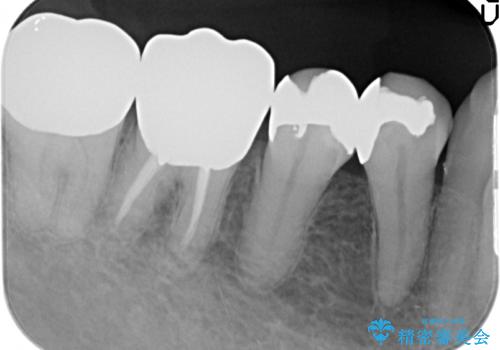

- 右下の古い銀歯のやり替えを希望された方の症例です。

口腔外から見えやすい 4 番目、5 番目の歯はセラミックによる審美的な治療を行い、6 番目、 7 番目の奥歯 2 歯は適合性に優れたPGA(ゴールド)クラウンによる治療を行いました。

- PGAクラウン…¥80,000×2、オールセラミッククラウン…¥100,000、仮歯…¥10,000×3、ファイバーコア…¥20,000、セラミックインレー…¥70,000費用は治療当時の料金となります